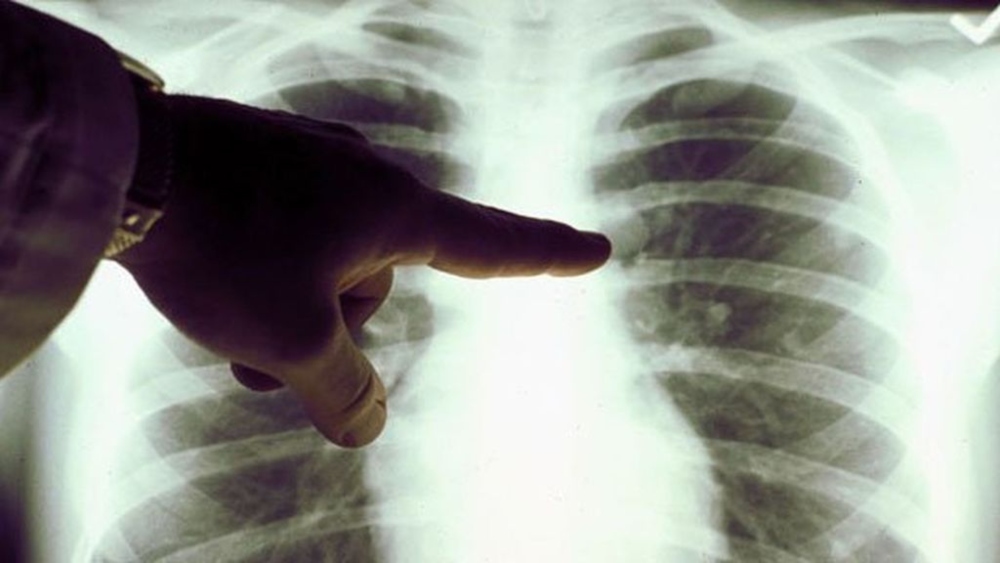

“El breve plazo entre el trasplante de pulmones y la aparición de la primera anomalía radiológica sugiere que la carcinogénesis comenzó en vida de la donante”, añaden los autores del trabajo. Un cáncer cuyo crecimiento se habría acelerado enormemente por los tratamientos inmunosupresores que la paciente recibió para evitar el rechazo a sus nuevos pulmones.